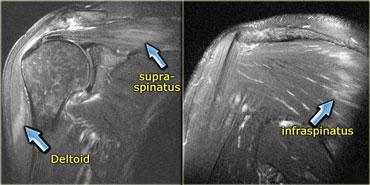

Các cơ thường bị tổn thương bao gồm cơ delta, cơ tứ đầu đùi (xem ví dụ tiếp theo), cơ gấp ngón tay và cơ gấp lưng cổ chân.

Mặc dù các hình ảnh không đặc hiệu, cần cân nhắc chẩn đoán này ở bệnh nhân cao tuổi có bất thường ở các cơ kể trên.

Hình bên trái là một bệnh nhân viêm cơ thể vùi.

Lưu ý tổn thương đối xứng của cơ tứ đầu đùi và sự vắng mặt của phù nề ở các tổ chức xung quanh.